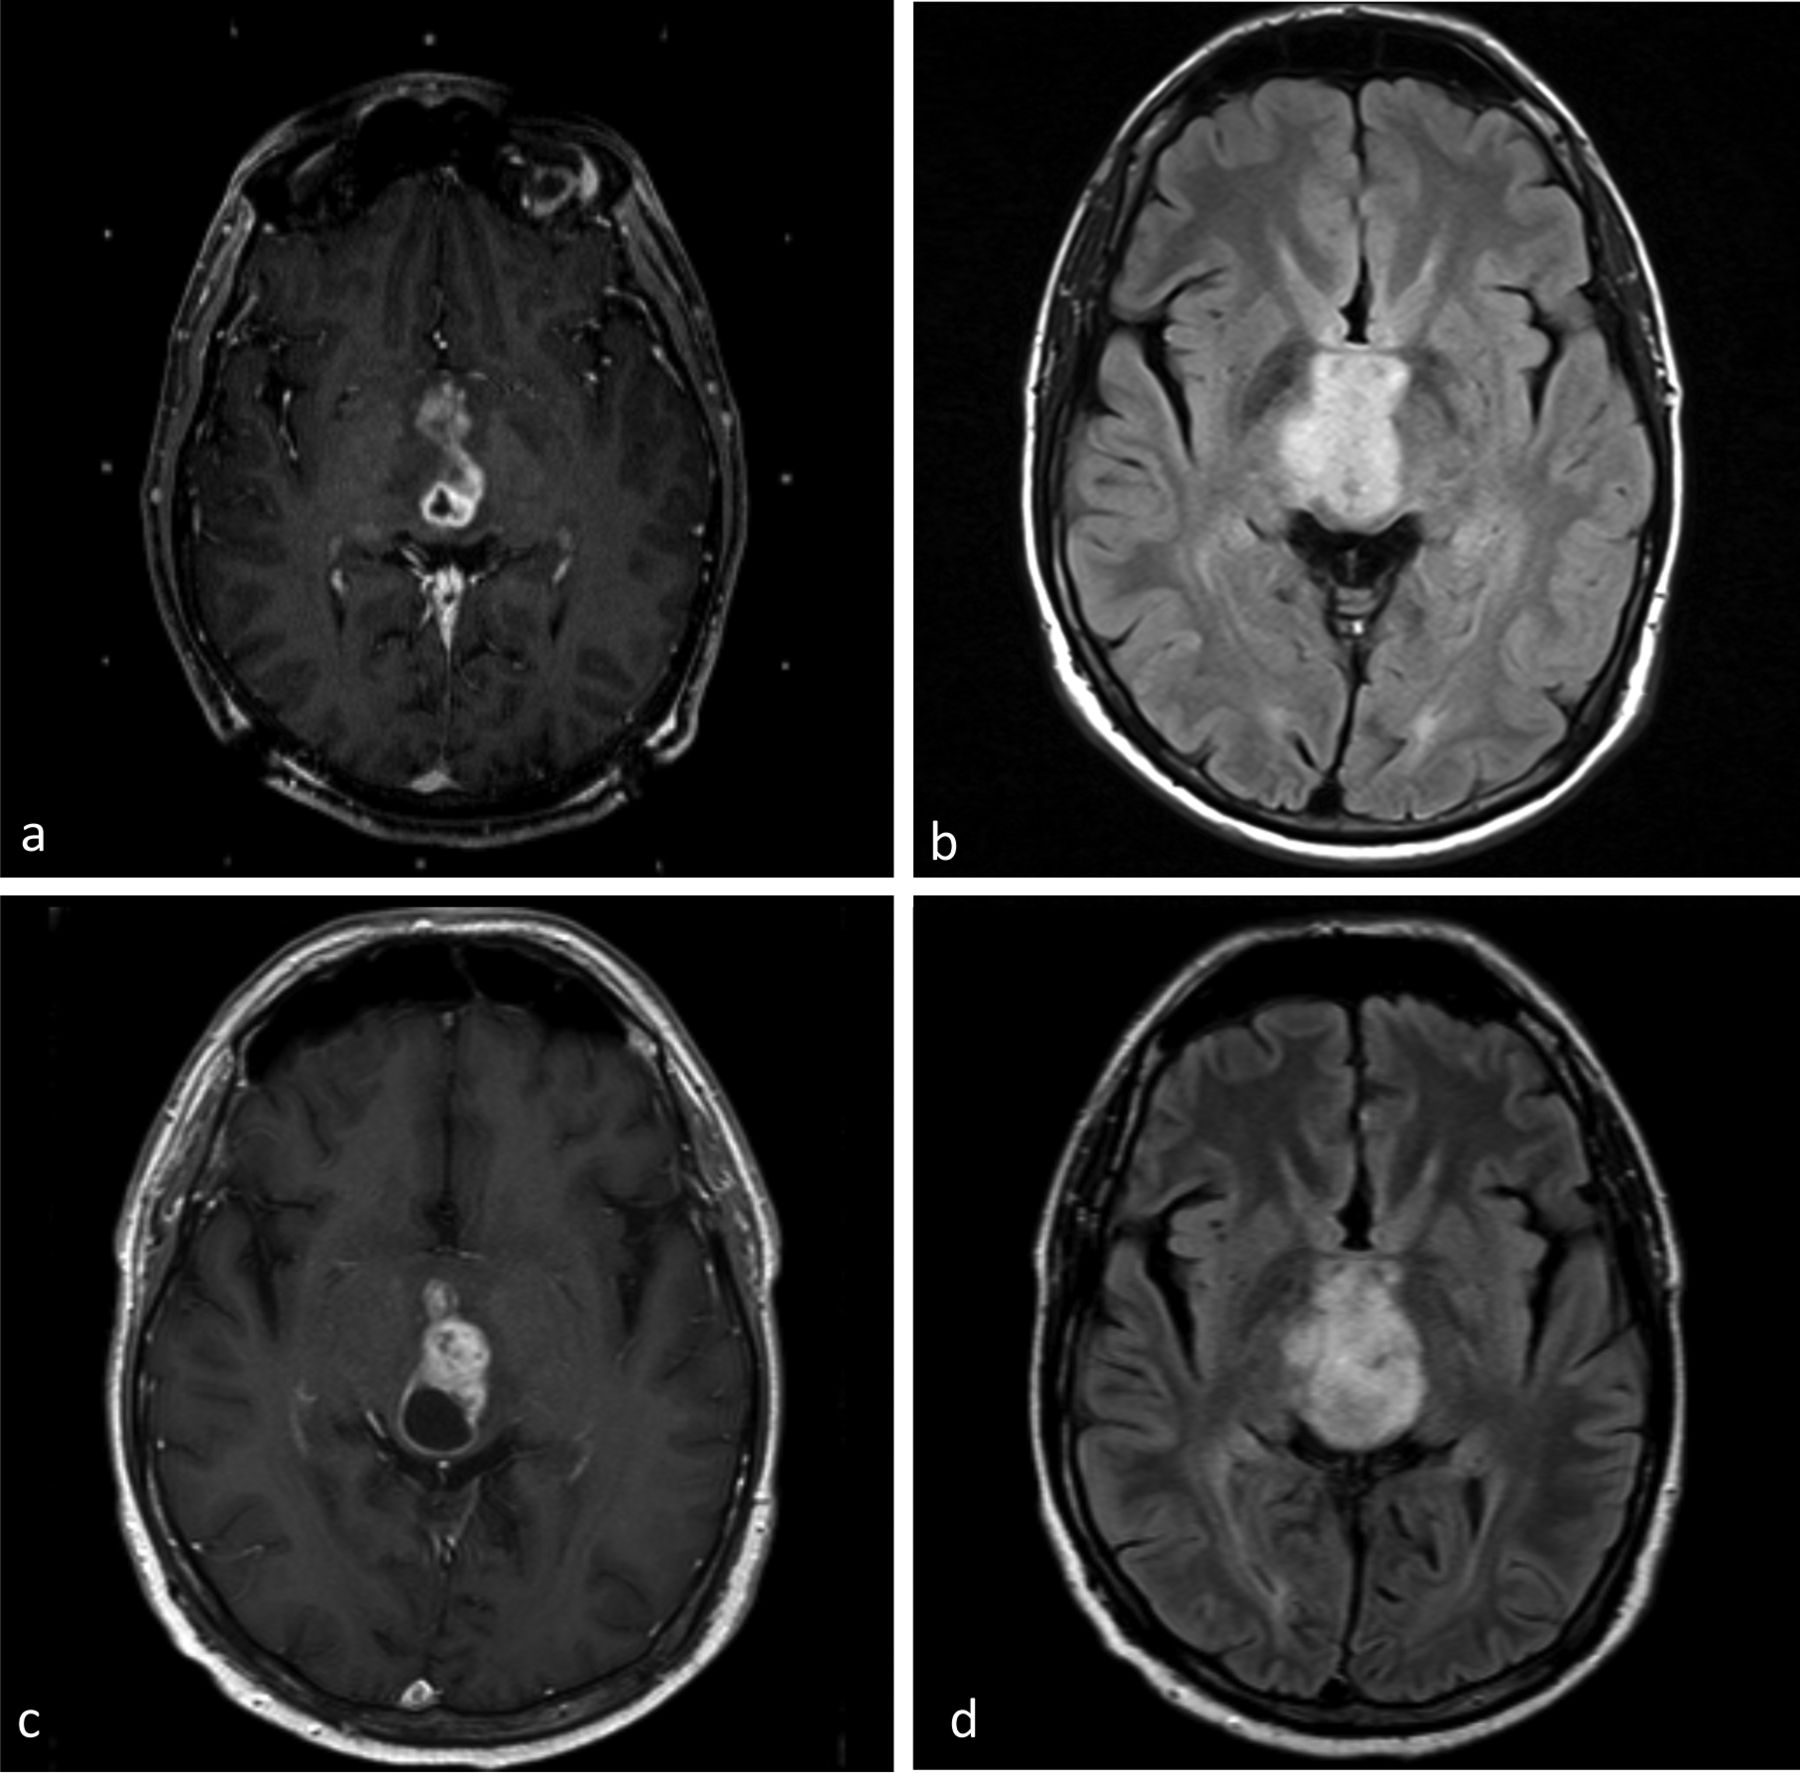

Glioblastoma, previously known as glioblastoma multiforme (GBM), is the most aggressive and most common type of cancer that originates in the brain, and has a very poor prognosis for survival.